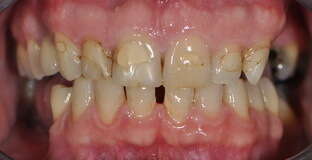

4. Couronnes céramiques sur incisives latérales et facettes sur incisives centrales